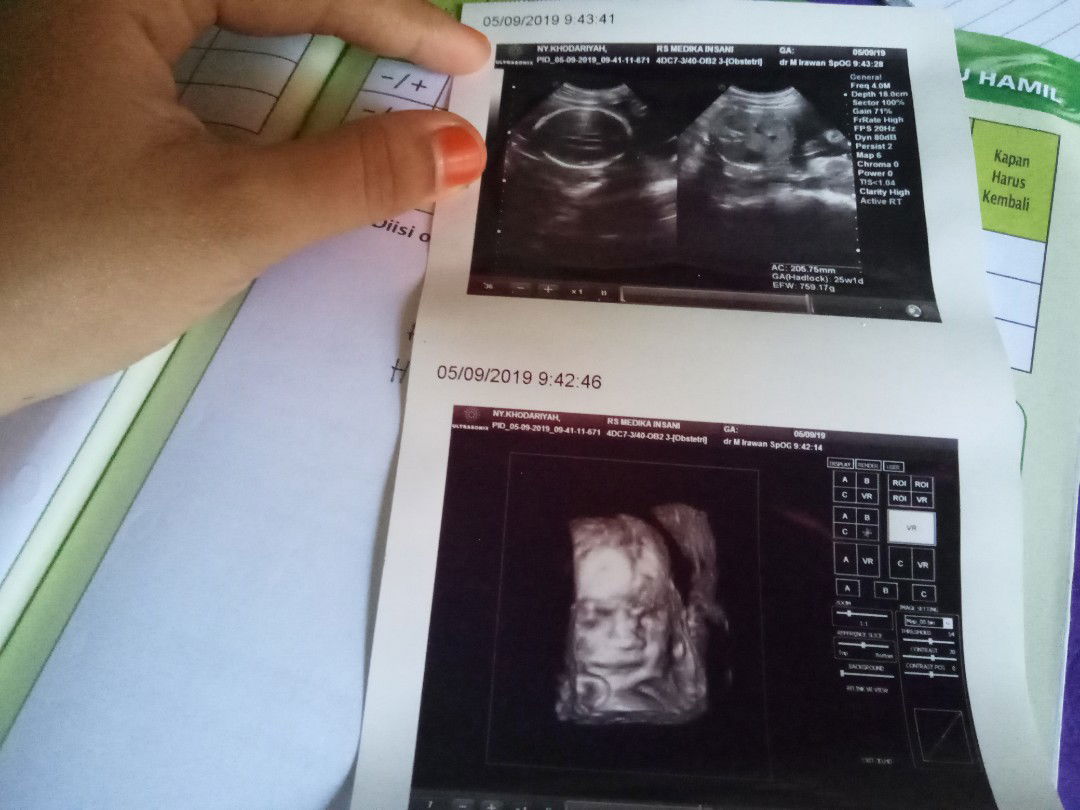

Coba diperiksakan ke dokter spog, atau gak USG. Soalnya setiap kondisi ibu hamil itu meskipun yg dirasakan sama blm tente hasilnya sama. Saya juga lagi hamil 35 w. Juga ngerasain hal yg hampir sama. Trs tulang miss v juga sakit, klw malam kadang susah tdr, sering kebelit pipis. Kemarin saya periksakan apakah benar si dedek sudah masuk panggul malah sebaliknya si dedek sungsang, air ketuban berlebihan yg bisa mengakibatkan bayi terlilit tali pusar. Trs saya disuruh puasa 8 jam utk tes lab juga. Jadi menurut saya lebih baik jika ada keluhan segera diperiksakan aja biar segera ada tindakan lebih lanjut.